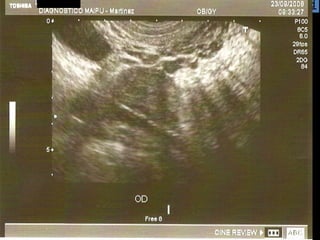

La ecografía ginecológica transrrectal es una ecografía endocavitaria que usa la vía transrrectal en lugar de la transvaginal. Se indica principalmente para pacientes vírgenes con ecografías ginecológicas no concluyentes, pacientes con vaginismo severo o hipotrofia marcada del introito y vagina. La técnica es similar a la ecografía transvaginal pero sin el tope vaginal, y permite imágenes casi idénticas.